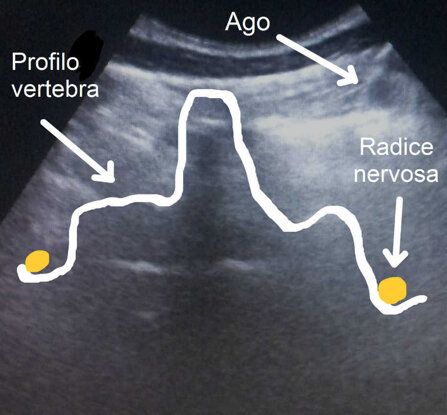

La via iuxtaforaminale prevede l’utilizzo contemporaneo dell’ecografo, con particolari programmi di visualizzazione della colonna vertebrale. L’ecografo permette di individuare il disco sede dall’ernia e inoculare sotto guida ecografica in real time la miscela dell’ossigeno-ozono vicino la radice infiammata.